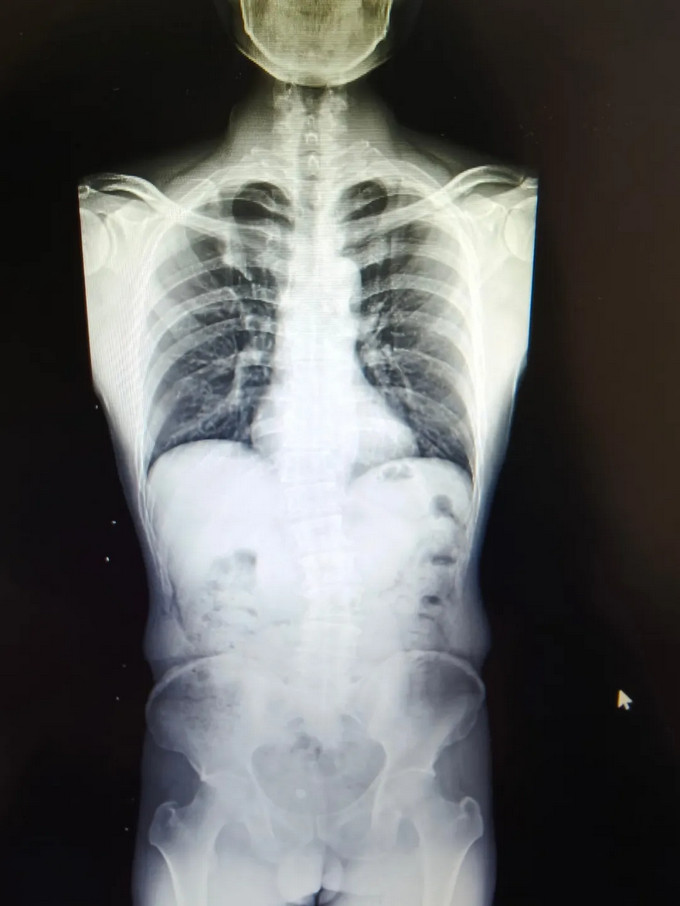

青少年小黄(化名),11岁,家属发现脊柱异常1年余。查体:双下肢真性长度等长,前屈试验阳性,ATR≥5°。全脊柱正侧位片示:“胸椎右侧弯畸形,Cobb角= 23.44 °”。

黄播 康复医学科诊疗团队诊断:“特发性脊柱侧弯”,为小黄制定完善的康复方案:一、脊柱侧弯健康宣教,二、基础运动训练(猫卷式、四点撑抗阻脊柱核心训练、侧平板、胸廓打开训练),三、传统康复训练(牵伸治疗、稳定性训练),柱侧弯得到明显矫正,复查全脊柱正侧位片示:“胸椎右侧弯畸形,Cobb角= 13.45 °”